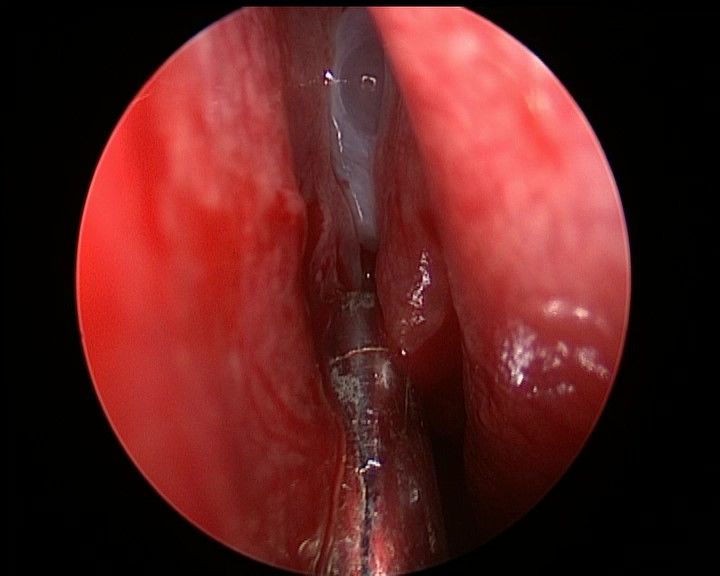

↑ 去除鼻中隔观察鼻腔后壁结构